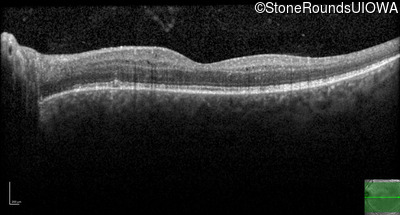

Optical Coherence Tomography - Right - 20/25

Exemplar / OCT Stack